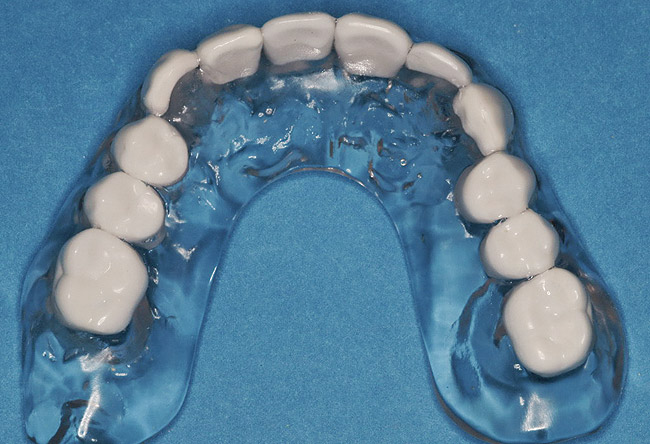

Figure 21  Five months after sinus and ridge augmentation healthy soft tissues were evident and the maxillary ridge was symmetric in the anterior sextant, where one side was originally deficient in ridge width.

Figure 21

Figure 22  Surgical template, supported by the four remaining teeth and soft tissues. Sequential computer-guided implant placement was used to further stabilize subsequent implant insertions.

Figure 22

Figure 23  Implant placement in the Nos. 7, 8, and 9 positions. Because the mesh did not require removal, flapless placement was possible. Note that it is visually impossible to distinguish between which side (right or left) was augmented with rhBMP-2 alone and which side was grafted with rhBMP-2 plus PLGA mesh.

Figure 23